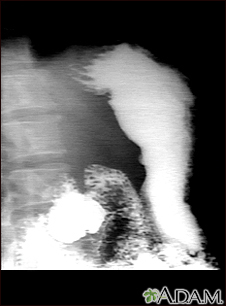

Stomach ulcer, x-ray